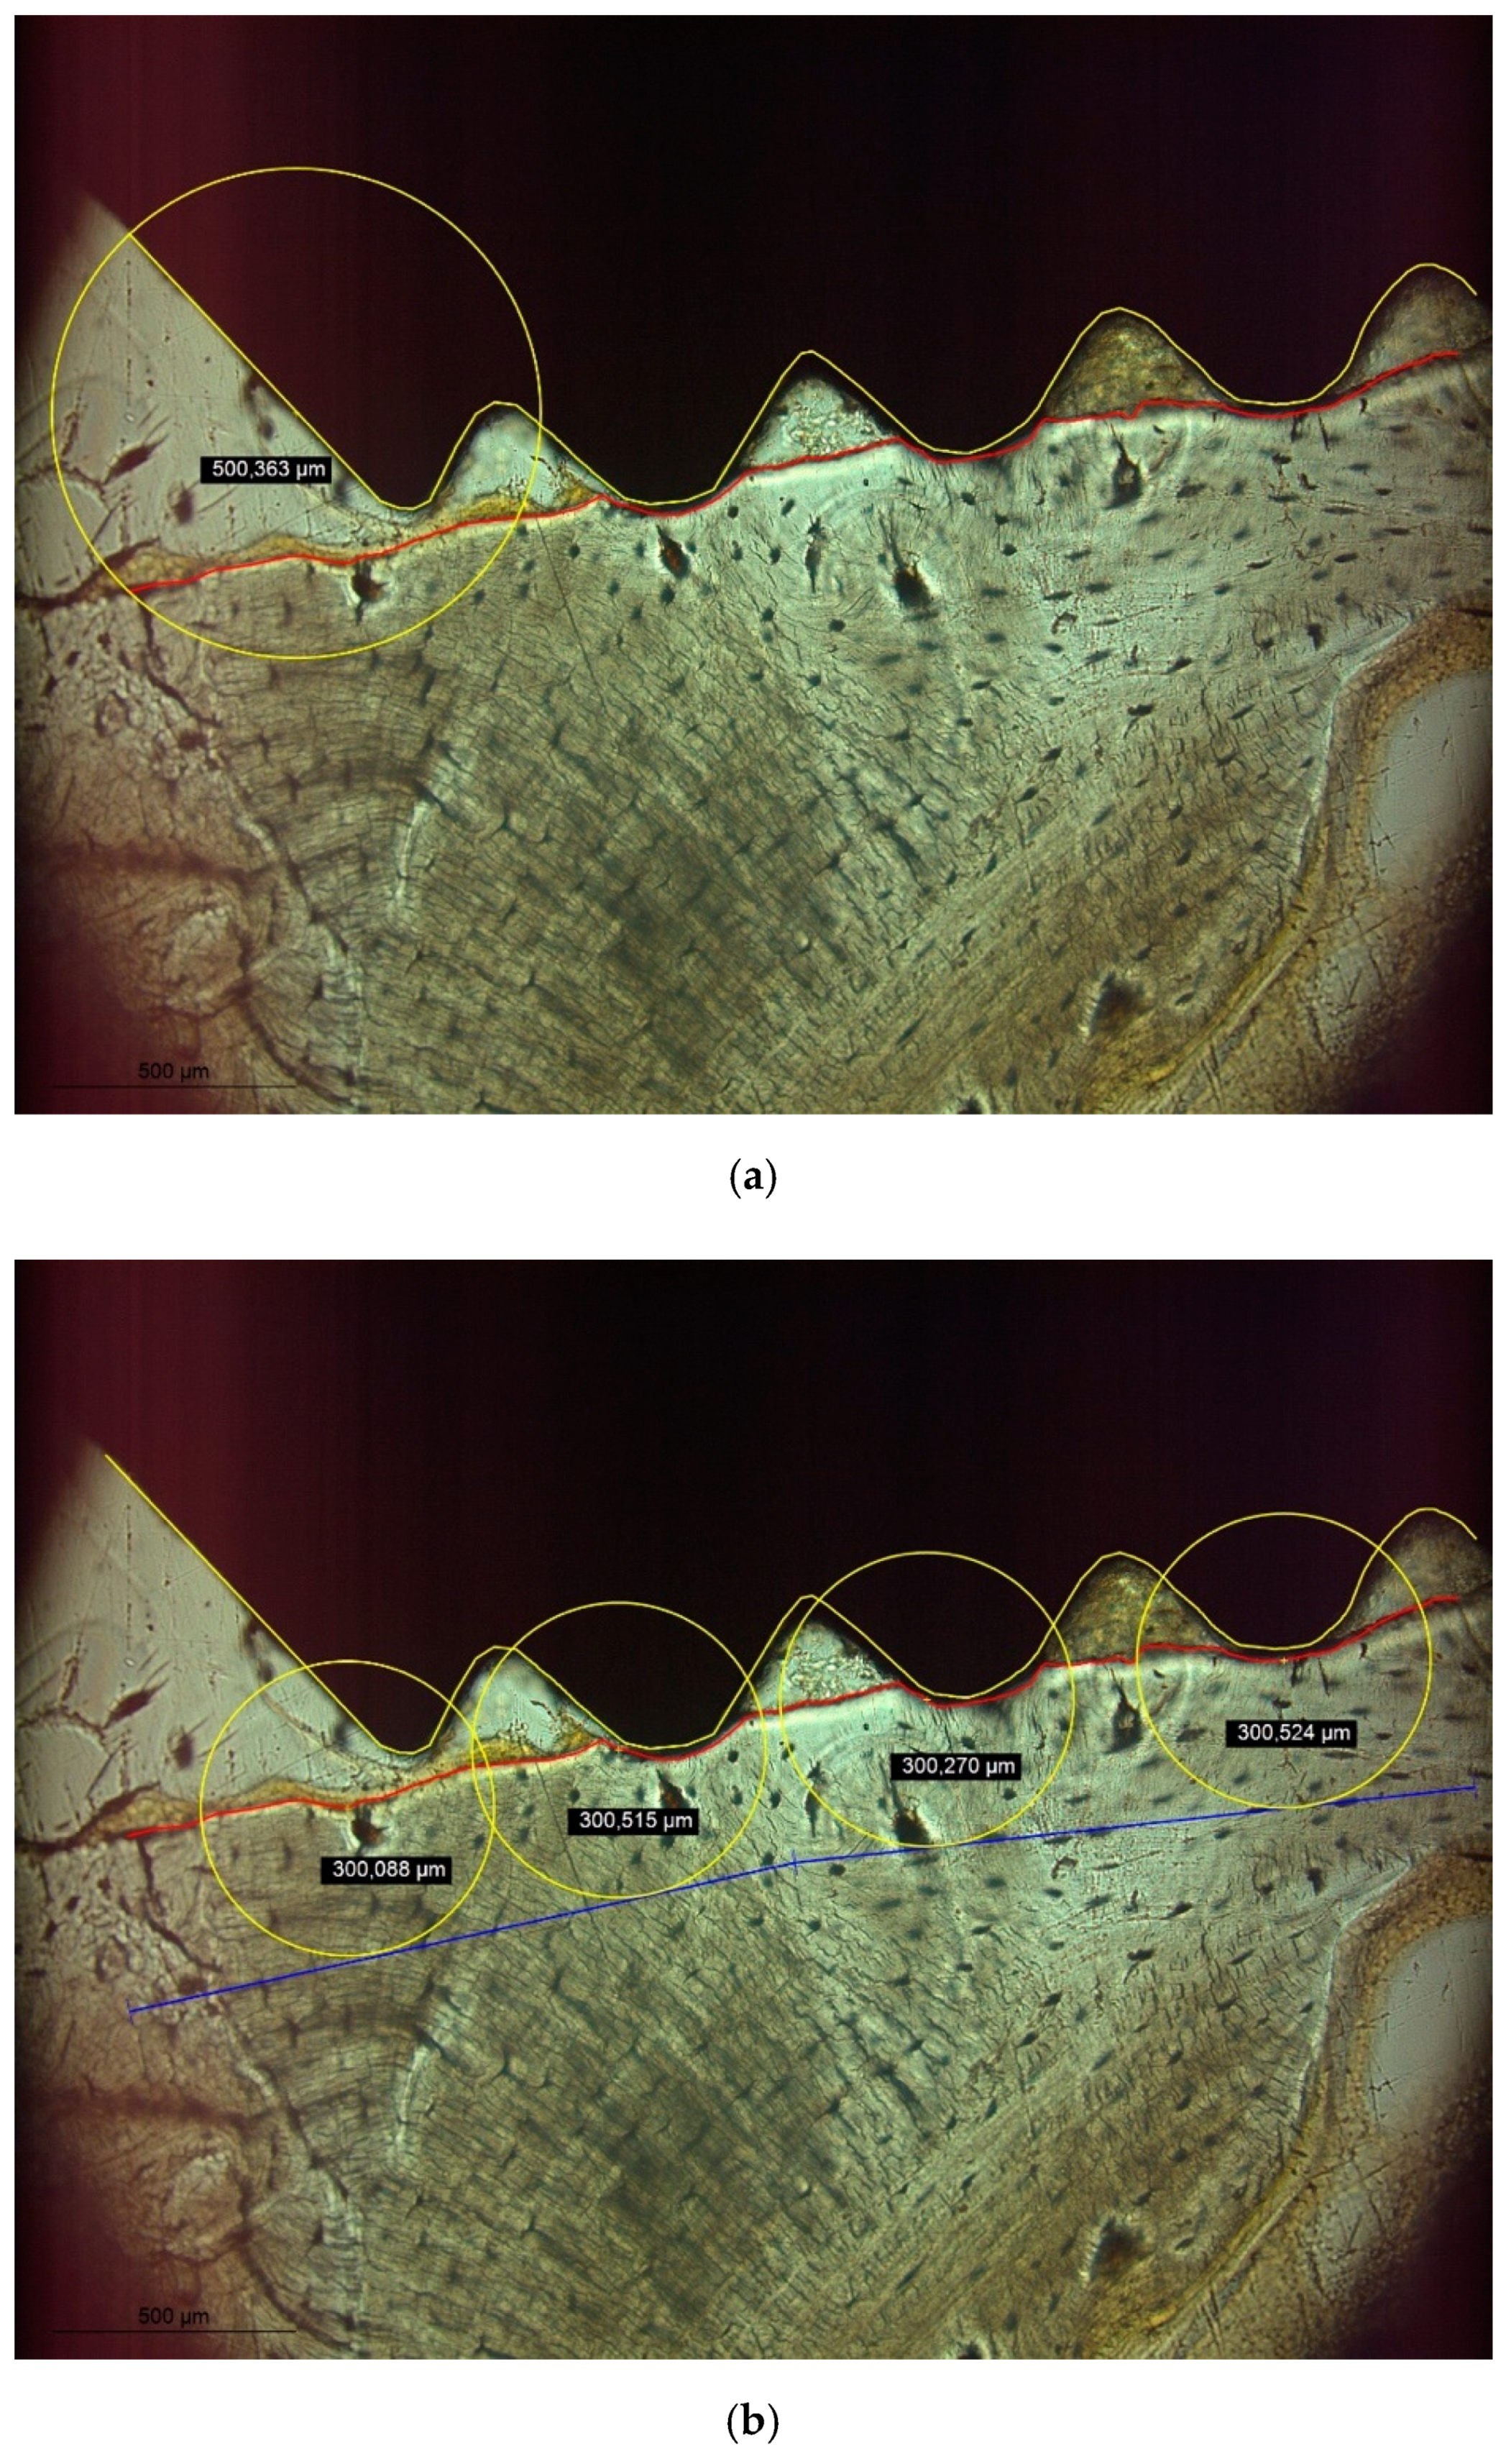

2.2. Histologic Analysis

3. Results